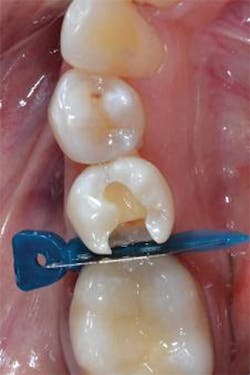

Figure 2: Preparation of tooth No. 29 with the Palodent Plus WedgeGuard in place. Placement of the WedgeGuard allows for faster preparation and increased confidence that iatrogenic damage can be prevented.